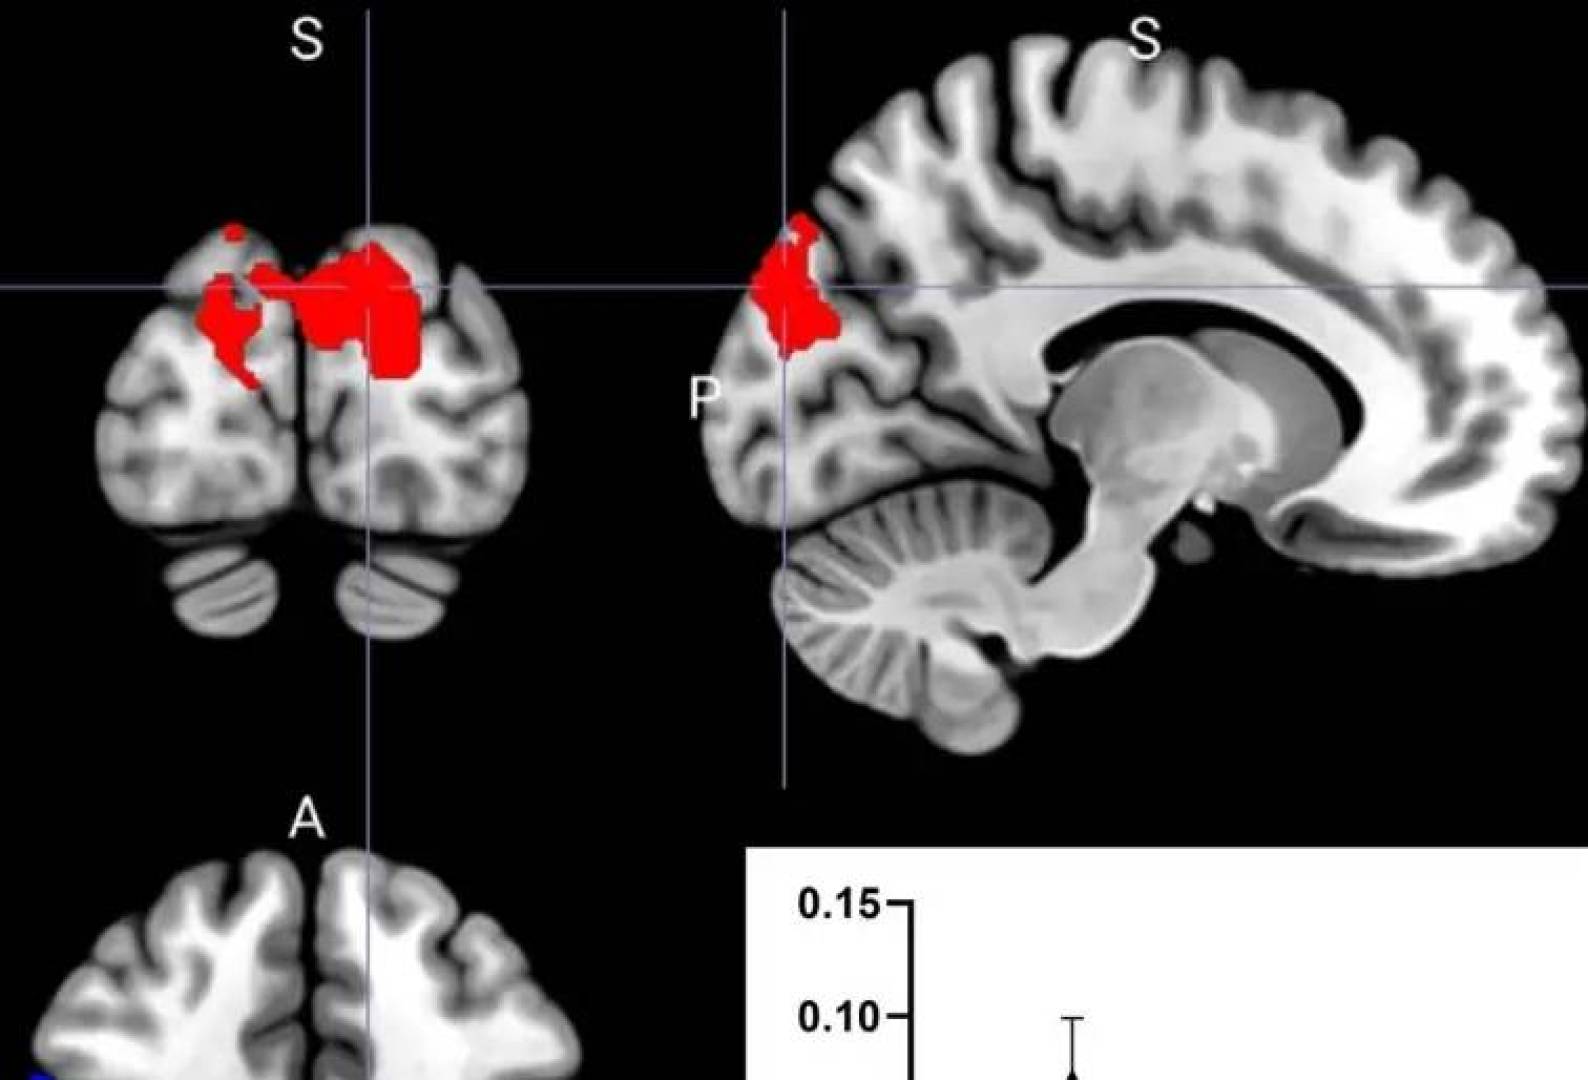

طريقة تناول البروبيوتيك—كبسولات أم مسحوق—تؤثر بشكل مختلف على الدماغ

أظهرت دراسة جديدة من جامعة أوريبرو Örebro University أن شكل تناول —سواء كبسولات أو مسحوق—يؤثر البروبيوتيك على كيفية تأثيره على الدماغ. تم نشر…